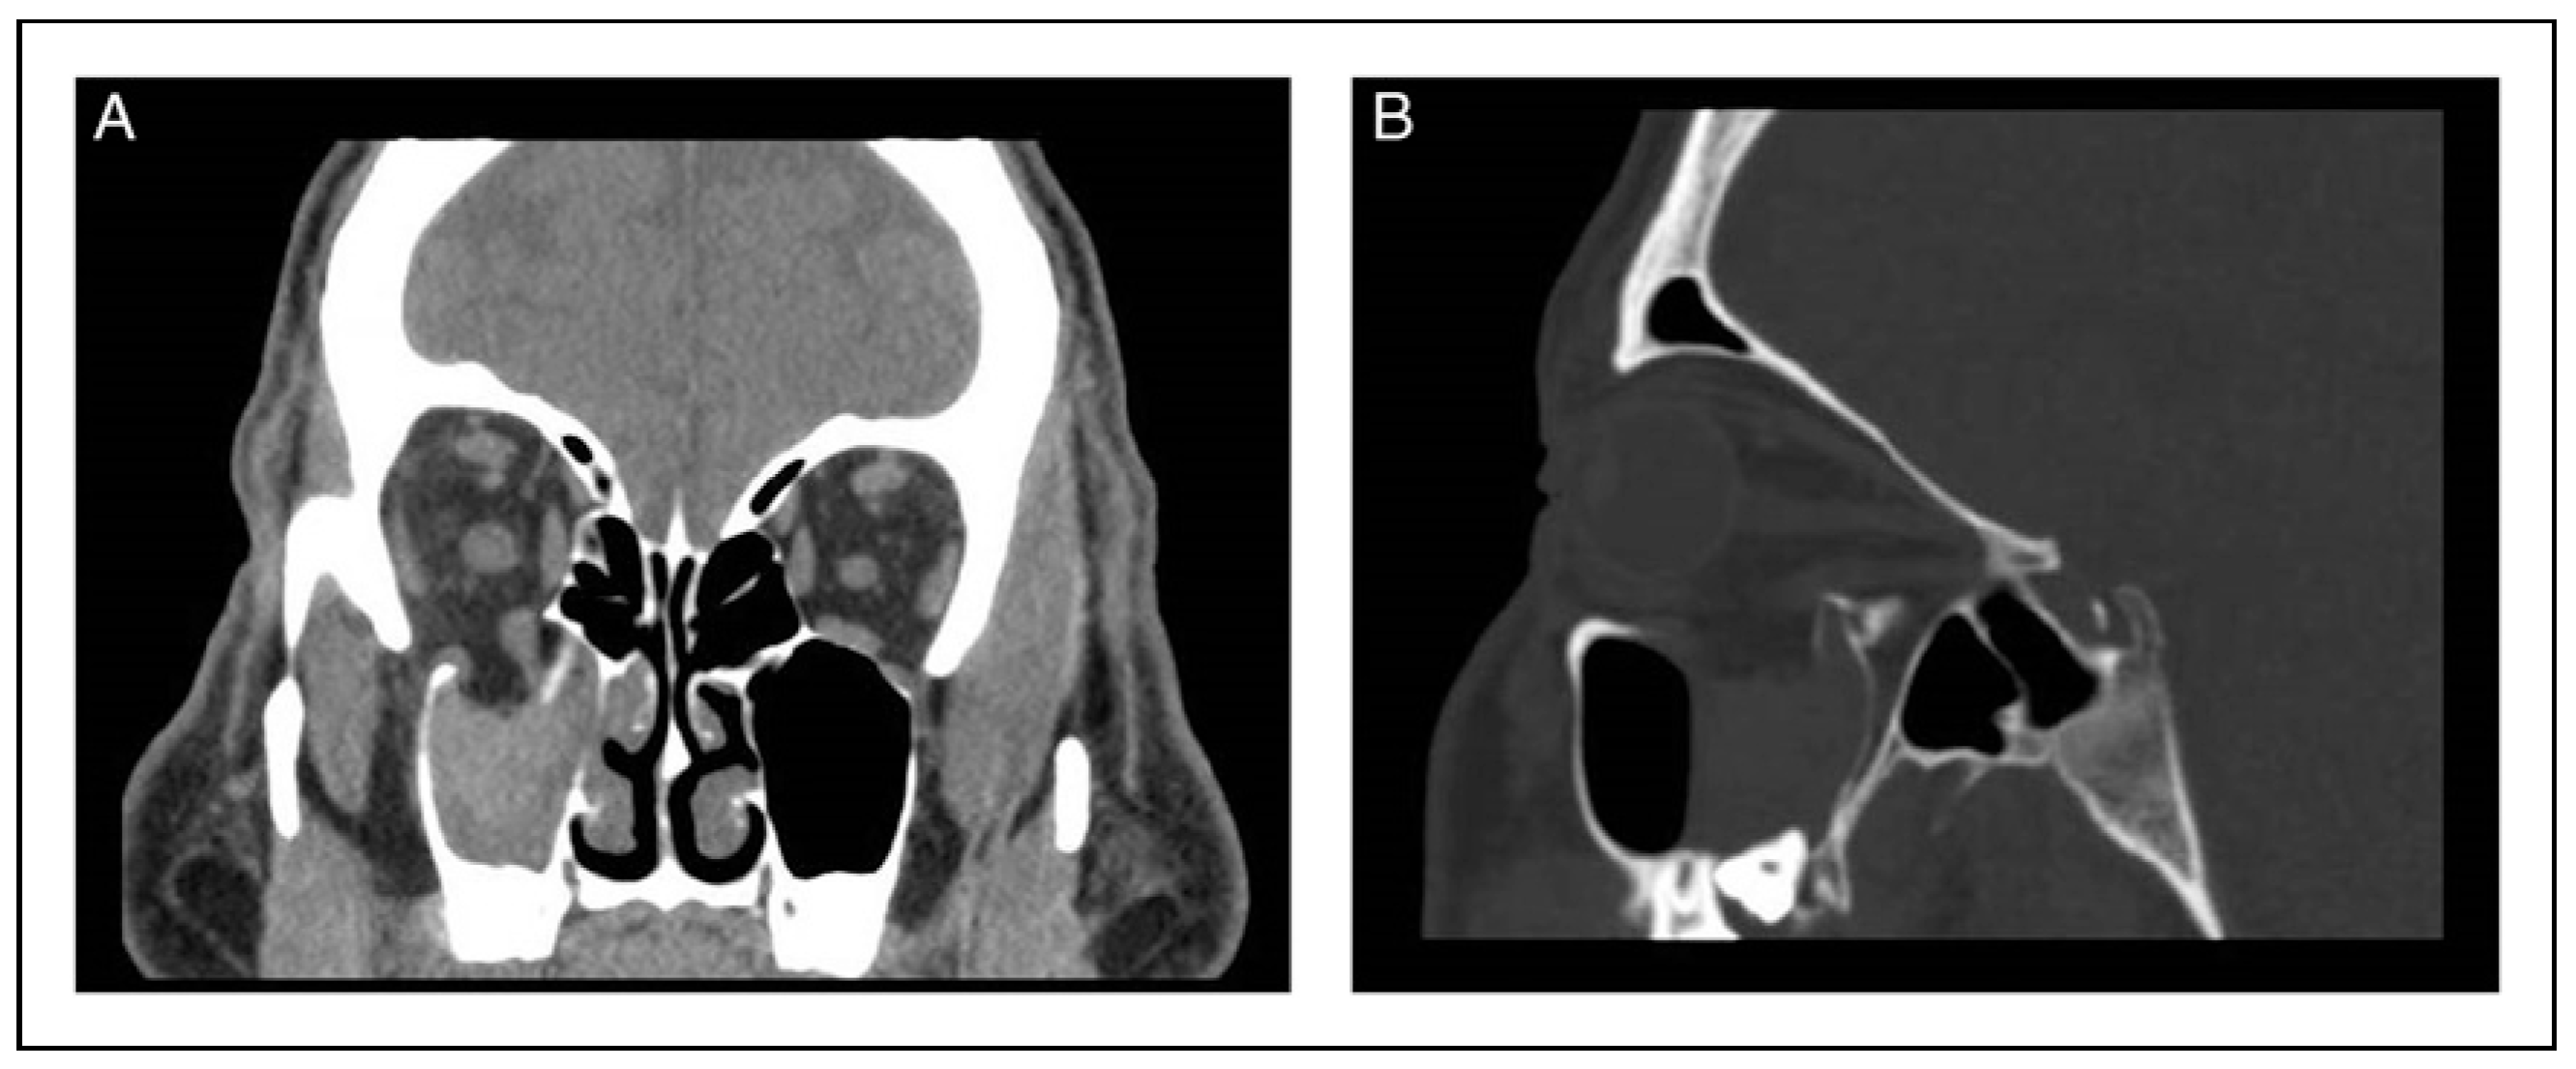

Finally, CT can be used either by measuring the difference between mirror image overlay or constructing a perpendicular along the orbital apex to a line drawn between the lateral orbital rims. Of note, one can use the posterior surface of the cornea as a stopping point when the anterior surface is difficult to define (Figure 5A,B). This analysis is quick and easy, especially initially in patients who likely already have a CT facial protocol in the context of facial trauma. CTappears to be the most reliable technique for assessment of enophthalmos based on interobserver variation data [5]. However, enophthalmos often develops later, after pneumo-orbital, swelling from edema and a possible hematoma have subsided. Even patients with a significant orbital floor fracture generally initially present with proptosis. Obtaining a repeat or serial CT may not be practical or preferrable over exophthalmetric measurements for the patient given additional unnecessary costs and radiation exposure.

As another example, the patient in Figure 5A,B is a 71-year-old male who suffered a right orbital floor blow-out fracture after a skiing accident. He developed late enophthalmos of >2 mm by CT exophthalmometry and 3–4 mm by Naugle measurement. He is an avid ski instructor and chose non-operative management after a long discussion, because of fears of possibly developing diplopia. His enophthalmos was evident to his wife, but not the casual observer. His only complaint was with his fitting of hard contact lenses on his enophthalmic side. This visual problem was subsequently addressed with a correctional lens when he had cataract surgery.

Figure 5. (A) CT exophthalmometry. A horizontal line is first made connecting the lateral orbital rims, and perpendicular lines extend to the posterior corneal surfaces. (B) Coronal CT demonstrating right orbital floor fracture which resulted in enophthalmos.